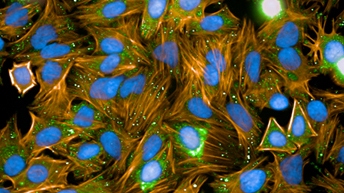

Scientists, philosophers, and artists alike are mesmerized by the brain, likening this 3 lbs of matter to a computer, a great factory, a beautiful mess, a world of unknown territory —or the most complicated object in the known universe. To even begin to understand the complex structure and function of the nervous system, including the brain, neuroscience researchers need to rely on innovative technologies, including analytical, cellular, and molecular biology, and imaging technologies.

To enable researchers to do their best research, Revvity offers a product portfolio that delivers on robust reagents and dependable instruments to help elucidate mechanisms that may better explain disease development and accelerate molecular biomarker and therapeutic discoveries.